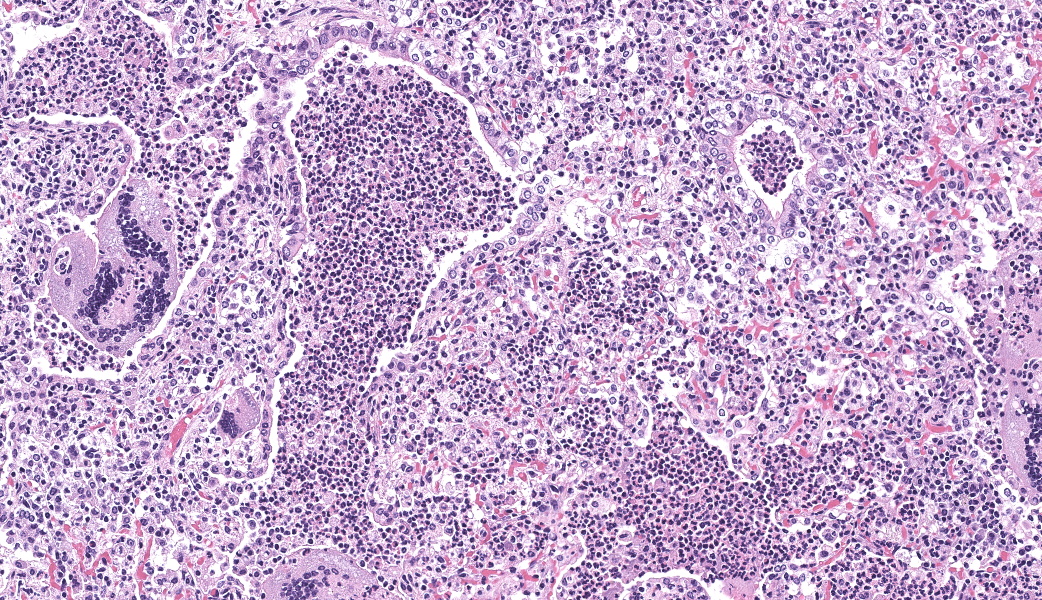

Lung, multiple sections. Within a single section of lung, approximately 75% of the bronchial, bronchiolar, and alveolar lumina contain overall large numbers of neutrophils, macrophages, large multinucleated cells, cellular debris, homogenous eosinophilic material, fibrillary eosinophilic material, and occasionally scattered erythrocytes. The multinucleated cells are often large and bizarre in appearance, some containing approximately 40 nuclei. The cytoplasm of these multinucleated cells is eosinophilic and variably granular to homogenous. A subset of these multinucleated cells contains few distinct optically clear vacuoles, while others demonstrate phagocytosis of few neutrophils. There is mild vascular congestion throughout, and there are small clusters of lymphocytes cuffing airways multifocally.Contributor's Morphologic Diagnoses:

Pneumonia, bronchoalveolar, suppurative, histiocytic, focal, subacute, severe with intraluminal multinucleated giant cells.Contributor's Comment:

Lung: Bronchopneumonia, histiocytic and neutrophilic, chronic, multifocal to coalescing, severe, with numerous multinucleated giant cells.JPC Comment:

Our fourth conference this year was moderated by the esteemed Dr. Thomas Cecere from Virgina Tech. The JPC team was thrilled to have him back for the second year in a row. This first case provided a great discussion on diagnostic workups and the processes that the pathologist should consider when choosing next steps in a case. Here, the lungs were “chock-a-block” full with histiocytic and neutrophilic inflammation with numerous giant cells that one participant remarked as having “a million nuclei.” These were some of the most impressive giant cells that many participants had seen. The bacteria were very difficult to see on the H&E, but the pattern of inflammation and presence of such robust giant cells should clue one into the presence of infectious organisms. As such, next steps should include a full gamut of routine infectious organism stains, including gram stains, acid fast stains, and fungal stains (GMS, PAS). Given that these were performed by the contributor, only confirmatory GMS and Fite-Faraco (FF) stains were performed in house, which revealed weakly acid-fast, GMS-positive organisms within multinucleated giant cells. This is consistent with the Nocardia spp. that were identified by the contributor. Those “chef’s kiss” multinucleated giant cells, though, deserve some recognition here.The multinucleated giant cell macrophage is a truly remarkable physiologic phenomenon. How they are formed is poorly understood. The current understanding is that macrophages need to be present in chronic inflammation, where they are constantly exposed to pro-inflammatory cytokines, such as IFN-γ, IL-3, IL-4, IL-13, and GM-CSF, as well as pathogen-associated molecular patterns (PAMPs) and other mediators of inflammation.1 A common setting in which these “ingredients” are found is in fungal infections or when dealing with foreign bodies, both of which can sometimes be too large for inflammatory cells to phagocytose and handle on their own. In this environment, macrophages will be in close association with one another and will begin to express molecules on their cell surface that enable fusion with one another, including dendritic cell-specific transmembrane protein (DC-STAMP; major driver of fusion), β1 and β2 integrins, CD44 (hyaluronic acid receptor), CD47 (integrin-associated protein), macrophage fusion protein receptor (MFPR), fusion regulatory protein (FRP-1, also known as CD98), and P2X7 (an ATP-activated ion channel that results in pore formation).1

Now that the involved macrophages have fused together into their version of Infinity Man, they are better equipped with their combined powers to engulf larger threats. One of the mechanisms that multinucleated giant cells have at their disposal to combat pathogens is to produce abundant amounts of nitric oxide (NO), which is generally microbicidal via induced oxidative stress.3 However, Mycobacterium spp. and Nocardia spp. target macrophages as their preferred home within the body and are able to survive intracellularly by preventing fusion of the phagosome and lysosome. Additionally, they produce enzymes to help them combat the damaging effects of NO and other reactive oxygen species produced by macrophages. Multinucleated giant cells are, for all their pathogen-fighting abilities, rather permissive to the persistence of Mycobacterium spp. and Nocardia spp. within them.3 With multinucleated giant cells pumping out a ton of NO, other macrophages are additionally induced to fuse and become multinucleated giant cells, which further perpetuates Mycobacterial survival and can contribute to the chronic nature of Mycobacterium spp. and/or Nocardia spp. infections.3